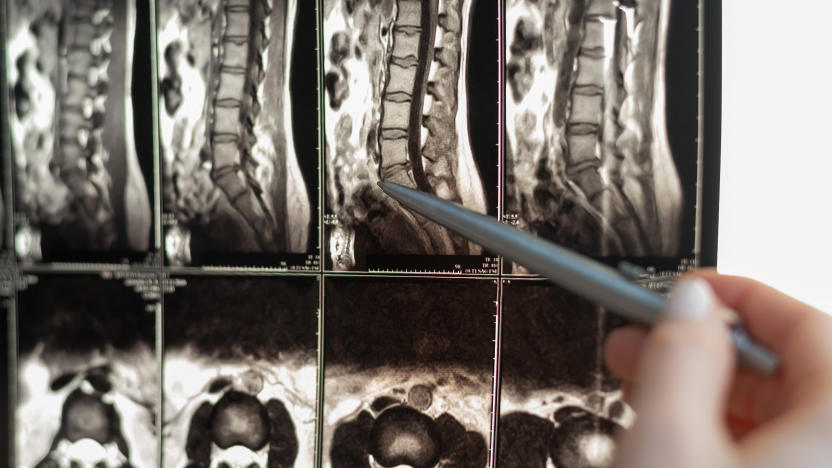

Jon Fingas03.23.2022AI discovery could advance the treatment of spinal cord injuries

Scientists have used a combination of AI and robotics to develop an enzyme that could treat spinal cord injuries and help people walk again.